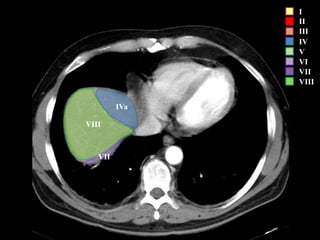

I

II

III

IV

V

VI

VII

VIII

IVa

I – Entre cava y porta

II – el más superior de los izquierdos

III – Por debajo del II

IV – por delante de la vesícula

V – por detrás de la vesícula

VI – relación con riñón derecho

VII – el más posterior de los segmentos superiores

VIII – domo hepático

Las claves de la segm. Hepática